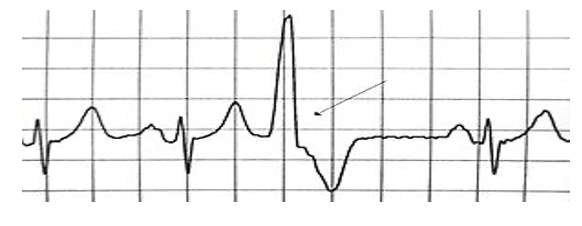

Figura 1: Retomando o conceito de extrassístole. Neste caso, temos umas extrassístole ventricular, um batimento precoce com QRS com morfologia e duração diferentes dos batimentos normais.

Figura 3: Batimento de escape juncional. Perceba o atraso ou a demora do segundo batimento em aparecer no traçado. O escape por natureza é um batimento tardio.

Uma das principais diferenças, portanto, que nos ajudam na hora de diferenciar extrassístoles de batimentos de escape, é justamente essa pausa que ocorre após o último batimento normal. Concorda que na figura acima, se após essa pausa, não viesse algum batimento de escape – nesse caso foi juncional (sem ondas P, logo não nascendo no tecido atrial ou nodo sinusal) -, entraríamos em assistolia? O termo “escape” faz juz ao fenômeno eletrofisiológico… Realmente, o coração escapa de entrar num ritmo de PCR.

Figura 5: Batimento de escape ventricular. Batimento tardio, com QRS com morfologia distinta do batimento normal e com duração aumentada.